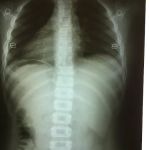

Welcome to our comprehensive guide on Dr. Matthew Yocom, DC, a distinguished chiropractor with a reputation for helping people in the Rockwall, Texas area recover from pain and get back to living their lives to the fullest. For those of us in the Lone Star State, finding a healthcare professional who is not only a skilled practitioner but also a true partner in recovery is invaluable. This article is crafted specifically for Texas residents, providing an in-depth look at what makes Dr. Yocom a premier choice for those dealing with a wide range of musculoskeletal issues, from chronic lower back pain to sports-related injuries. We understand that you want a provider who is attentive, professional, and dedicated to your long-term wellness, and the experiences of Dr. Yocom's patients consistently highlight these very qualities.

The philosophy behind Dr. Yocom's practice is rooted in effective, outcome-based treatment. His approach is not about temporary fixes but about achieving lasting results that enable you to return to the activities you love without pain. Patients have shared powerful stories of recovery, from a month-long battle with lower back pain disappearing after a few sessions, to regaining full range of motion in their arms after struggling for months. The emphasis on finding the source of the pain and then providing a clear treatment plan is a recurring theme in patient testimonials. Dr. Yocom is often praised for his ability to accurately diagnose and treat conditions, often in a shorter timeframe than traditional methods, helping patients avoid more costly or invasive procedures. His dedication extends beyond the clinic, as he has been known to check in on his patients' progress, demonstrating a genuine commitment to their well-being.

Dr. Matthew Yocom is known for providing a variety of services aimed at pain relief and injury recovery, often in collaboration with other professionals. His approach is focused on targeted, hands-on treatment that helps patients get back to their normal routines quickly and effectively.

- Spinal and Joint Treatments: While the provided information does not explicitly state "chiropractic adjustments," reviews highlight his hands-on treatments for back pain, shoulder pain, and other joint issues, which are core to a chiropractor's practice.

- Pain Diagnosis and Treatment: He has a reputation for accurately diagnosing the source of a patient's pain, such as knee pain or shoulder pain, and creating a clear treatment plan to address it.